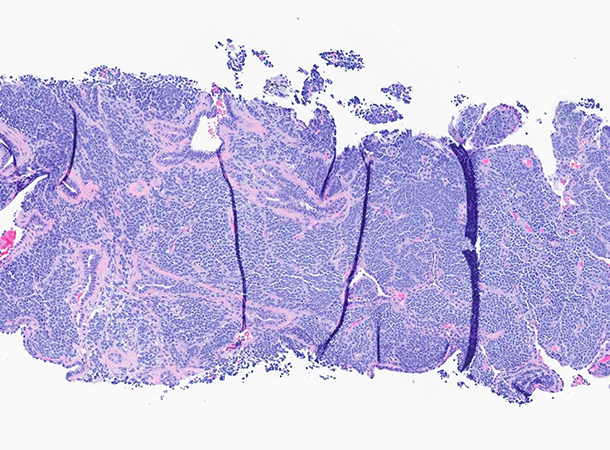

Histologically, these tumors are composed of a monotonous population of small round, uniform cells with scant clear or eosinophilic cytoplasm, indistinct cell borders, fine chromatin, and inconspicuous nucleoli (Figures 1 through 3). Tumors with more prominent neuroectodermal differentiation may have conspicuous Homer Wright rosettes, with groups of tumor cells arranged around a central fibrillary core. Commonly, there is necrosis, hemorrhage, or cystic changes. Immunohistochemistry is pivotal to distinguishing these tumors from other primary lung neoplasms. ES shows strong diffuse membranous CD99 (Figure 4) and nuclear NKX2.2 expression (Figure 5), the latter of which is more specific than the former. FLI-1 and ERG may also be positive in tumors with corresponding gene fusions. Additionally, these tumors are often positive for periodic acid–Schiff (PAS) and are diastase sensitive. A subset may stain with neuroendocrine markers (Figure 6), a potential pitfall in the differential diagnosis with small cell carcinoma. S100 expression may also be seen, raising the consideration of melanoma. ES is consistently negative for TTF-1, cytokeratins, and desmin.